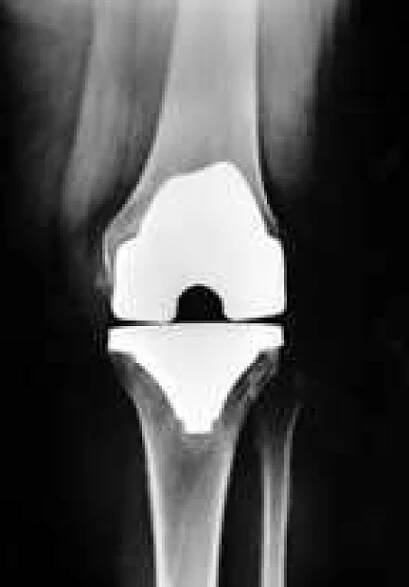

Obr. 4a: RTG obraz náhrady kolenního kloubu